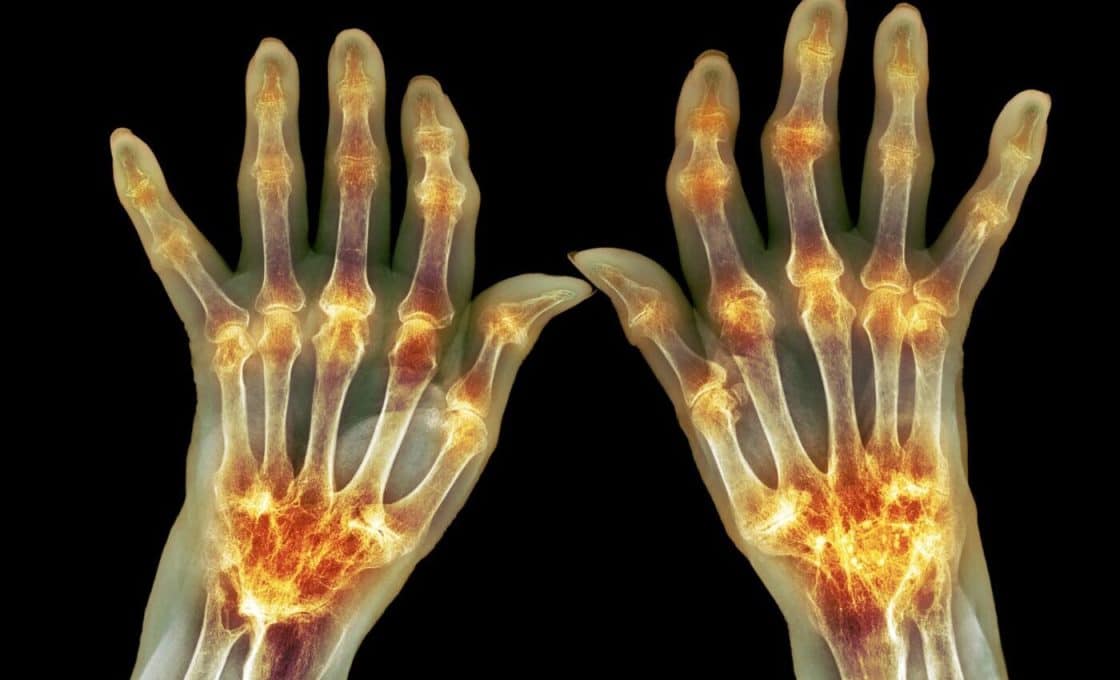

“Autoimmune diseases have risen steeply in the industrialized world,” the authors wrote. An estimated 18 million people worldwide are affected by rheumatoid arthritis, a chronic autoimmune disease-causing inflammation throughout the body and pain in the joints. Like other autoimmune diseases, RA is caused by the immune system attacking the body’s tissues and organs. Though the exact cause is unknown, genetics and environmental exposures—such as smoking and changes of gut commensal bacteria, or dysbiosis—are among the risk factors.